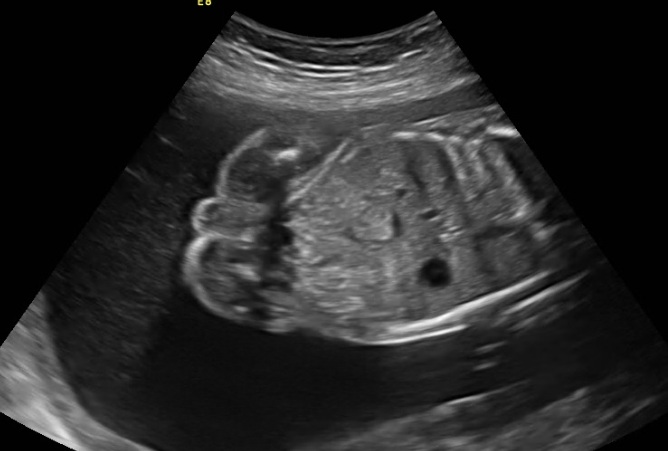

Посмотрите,кто по вашему ?

Пол малыша

на втором фото это могут быть половые губы ? если увеличить,то похоже. а сбоку что тогда ? но и на краник не особо похоже,както он сильно сбоку и вроде как отдельн.

Я, не чего понять не могу. На втором фоте, что то торчит, мальчик наверно.

На последней ракурс не до пола)))А на первой животик с органами и вроде как тоже ракурс не для пола,на второй мальчик

там на последней на 4д чтото есть внизу похожее на писюшку :)

я там четко вижу ножку на животе с пальчиками

Ну я могу сказать,что в таком ракурсе,даже на 37 нед у меня не было видно,а вот со стороны попы дааа))а что узист говорит?я смотрю 27 неделю,они что не могут до сих пор определить пол?😲

Чёт ничего не понимаю на ч/б фото, где что...

На последнем фото - вроде мальчик